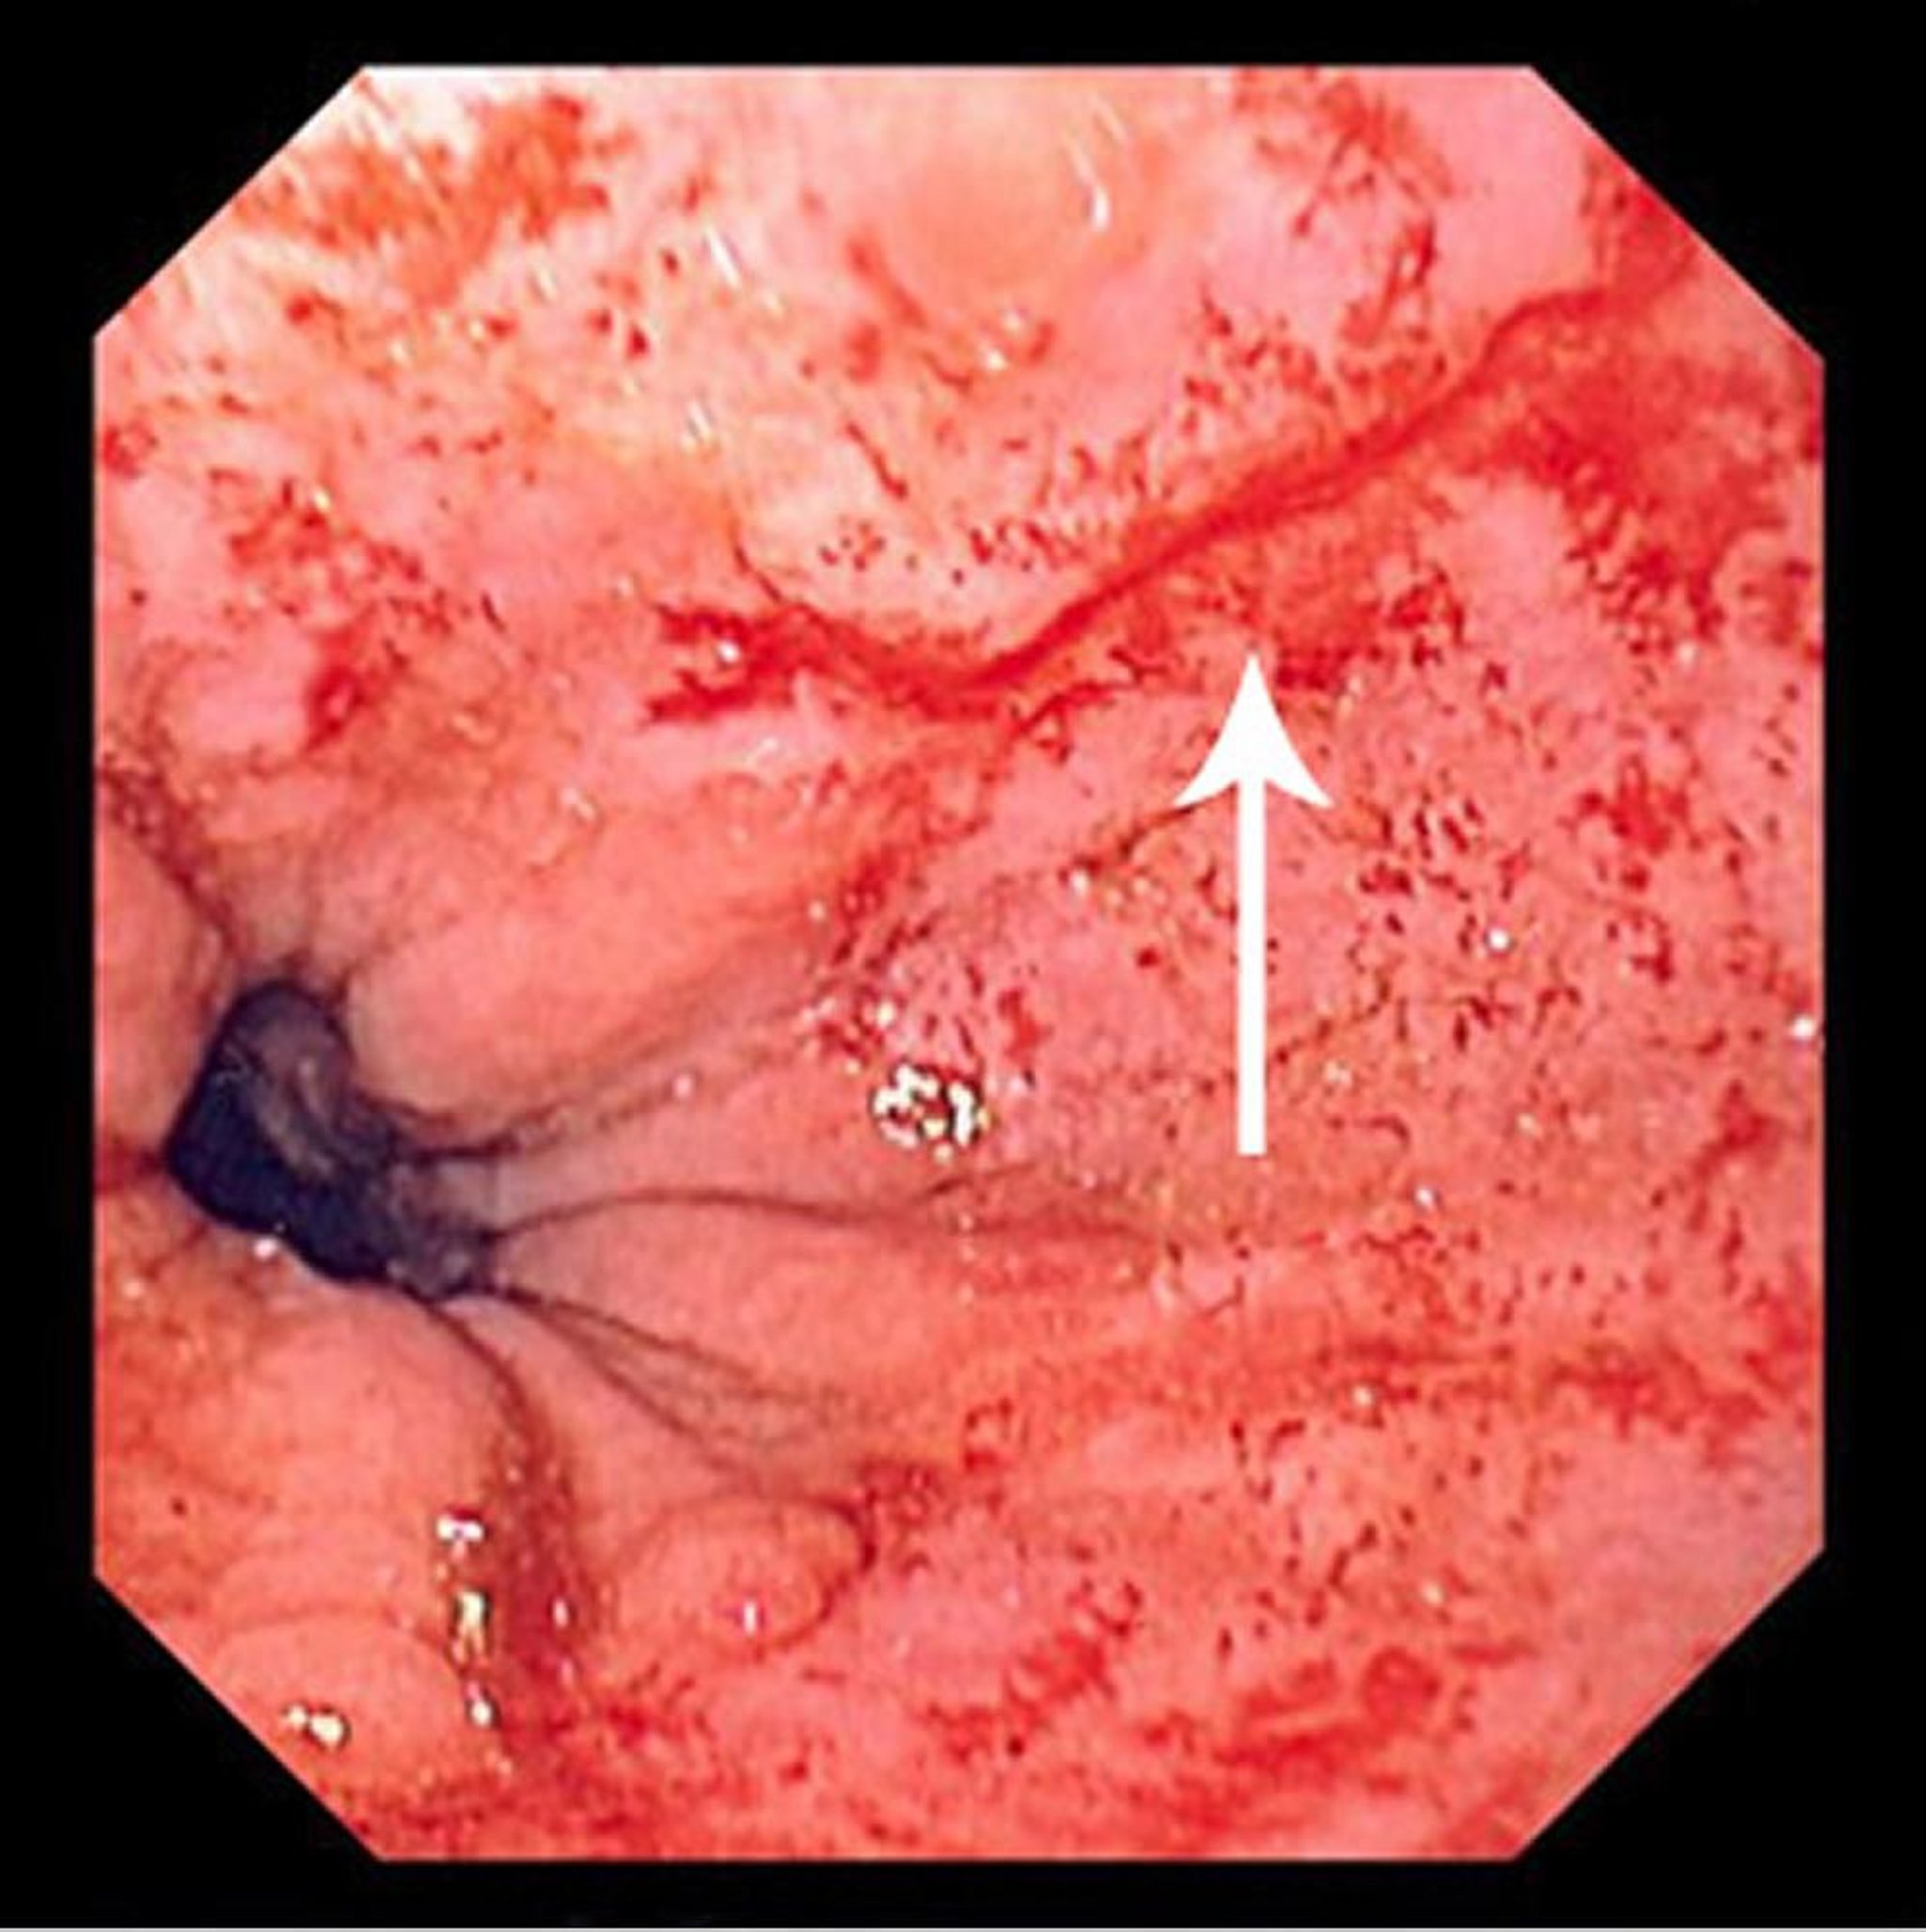

Déchirure de Mallory-Weiss

Cette image montre une fine déchirure linéaire (flèche) commençant juste au-dessus de la jonction squamocolonnaire et s'étendant proximalement.

Image provided by David M. Martin, MD.